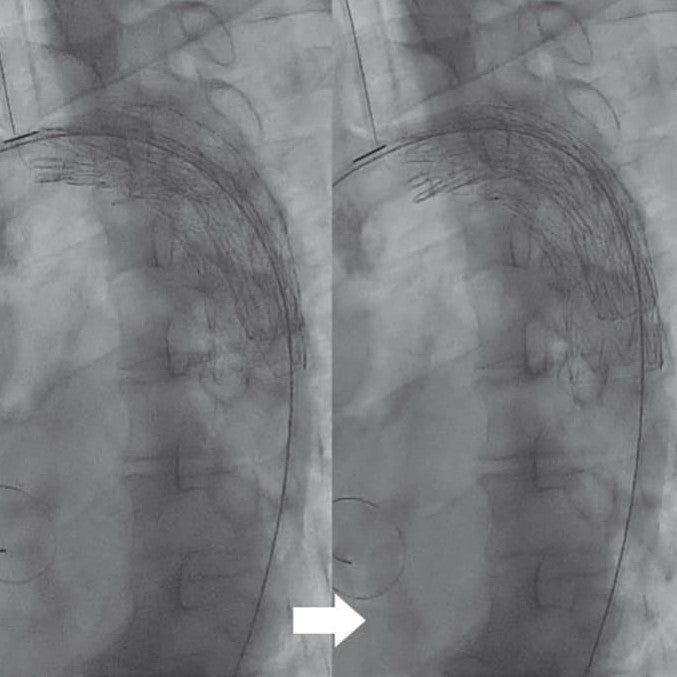

全身麻酔下、仰臥位にて手術を開始した。右鼠径部を切開し、右総大腿動脈をテーピング、タバコ縫合をおいた。ヘパリン投与後、右総大腿動脈から5 Frシースを挿入した。右総大腿動脈シースからピッグテールカテーテルを上行大動脈まで進め、ステントグラフト用ガイドワイヤーに変更、シースを20 Frゴア® ドライシール フレックス イントロデューサシースに入れ替えた。デバイスは末梢側からTAG® コンフォーマブル ステントグラフト28 mm × 10 cm、および31 mm × 10 cmを選択した。まず28 mm × 10 cmを左鎖骨下動脈末梢から留置、ついで31 mm × 10 cmを予定留置部位まで進め、造影で左総頚動脈および左鎖骨下動脈の位置を確認し、アンギュレーションコントロールダイヤルをゆっくり回しながらデバイス中枢の角度を慎重に大動脈に合わせた後に留置した。解離症例であるためバルーンによる圧着は施行せず、最終造影でエンドリークを含め異常のないことを確認し手技を終了した。手術時間は1時間11分であった。